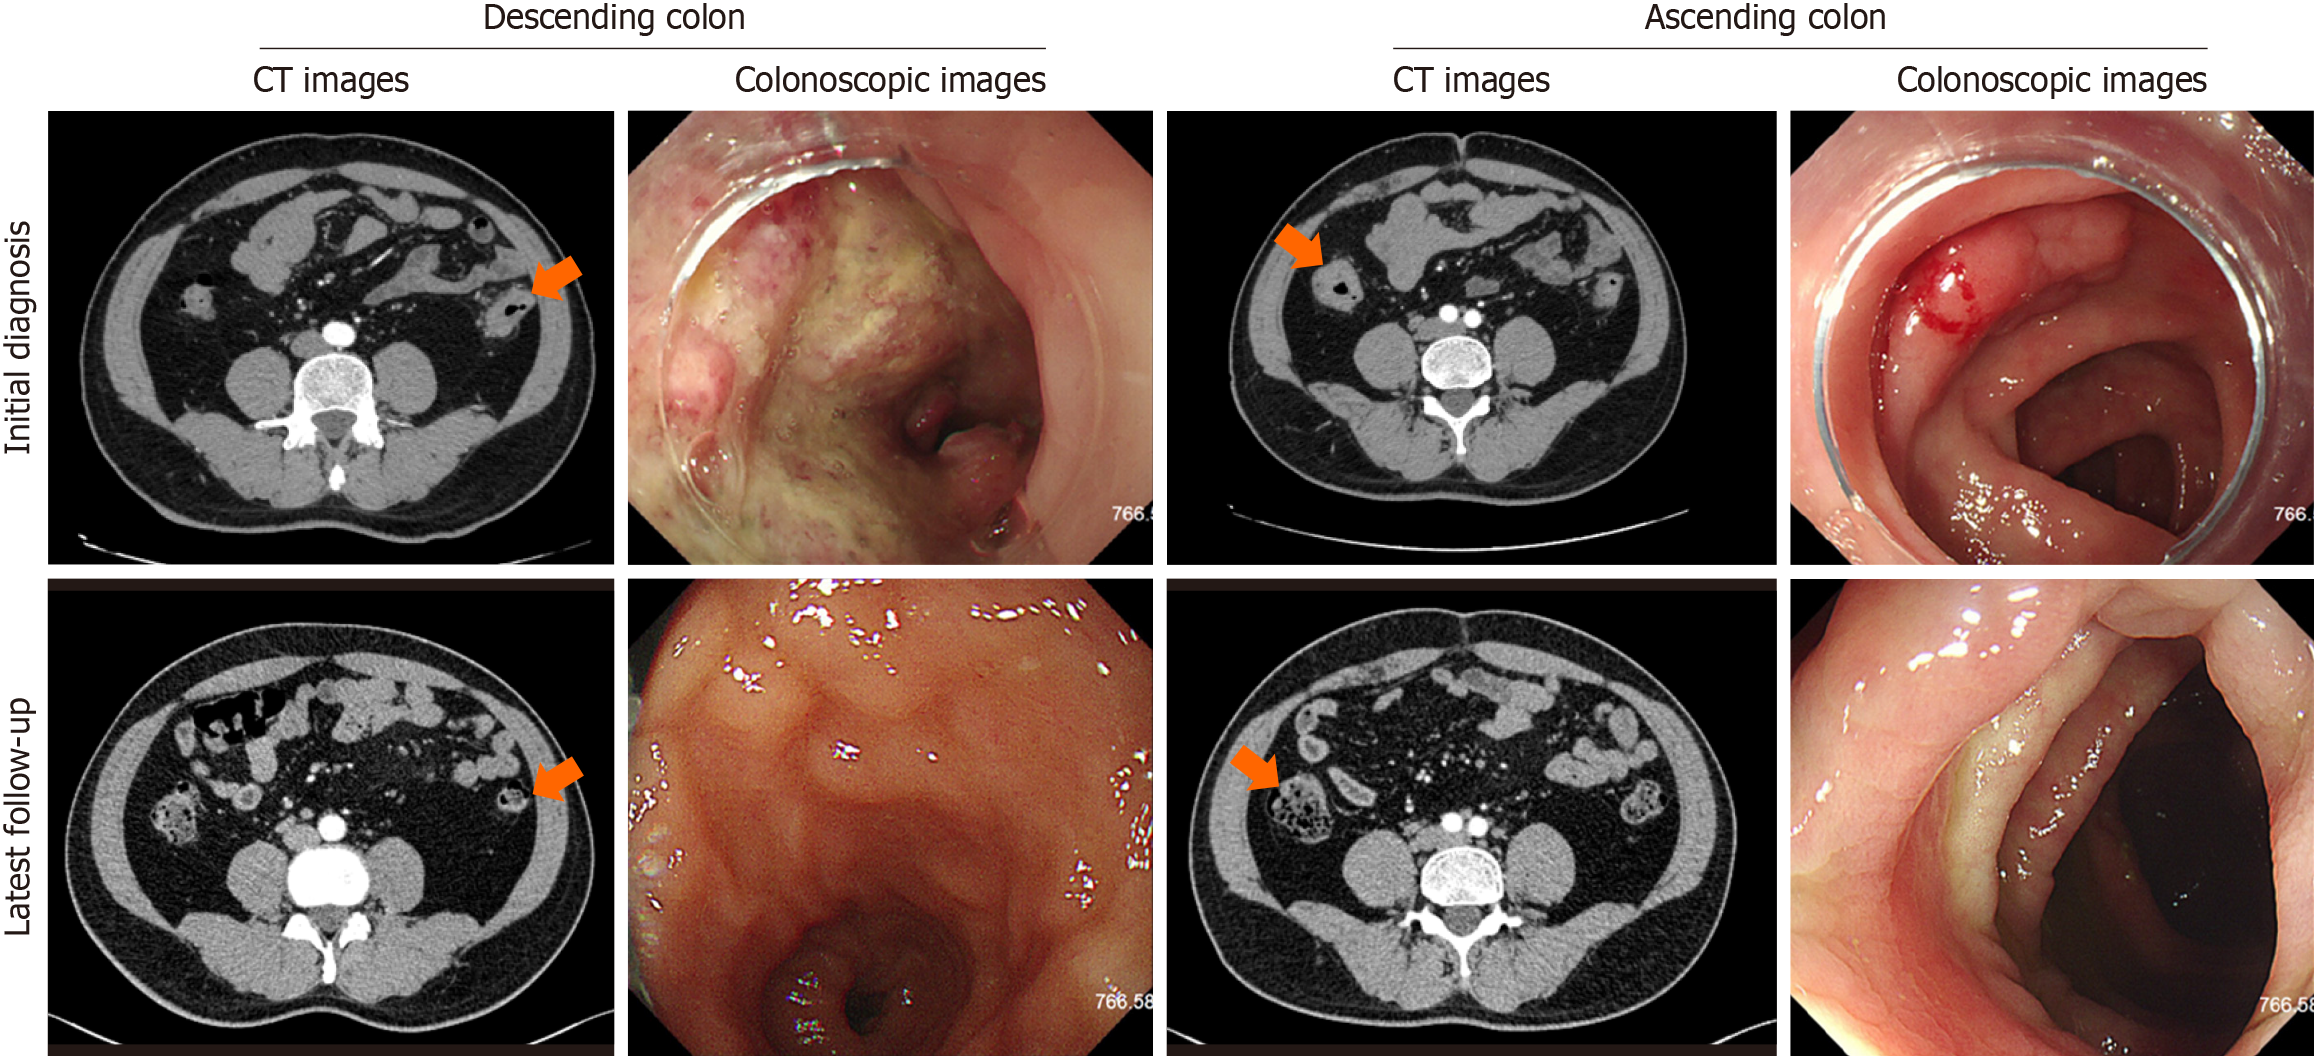

A colonoscopy identified multiple polyps in the colon and suspected malignant tumors in both the descending and ascending colon. Subsequent biopsies confirmed high-grade intraepithelial neoplasias in the ascending colon and poorly differentiated adenocarcinomas in the descending colon. The abdominal and pelvic computed tomography scans revealed mural thickening and enhancement in the colon, along with lymphadenopathy in the right iliac and bilateral inguinal regions, initially suggesting a stage IV disease (cT4N2-3M1). However, subsequent inguinal lymph node biopsy showed no evident neoplastic diseases, leading to a revised diagnosis of stage III (cT4N2-3M0). The patient underwent treatment, and follow-up computed tomography scans post-treatment demonstrated resolution of the mural thickening and enhancement in the colon, with significant reduction in the size and number of lymph nodes in the right iliac and bilateral inguinal regions, indicating a good response to therapy (Figure 2).